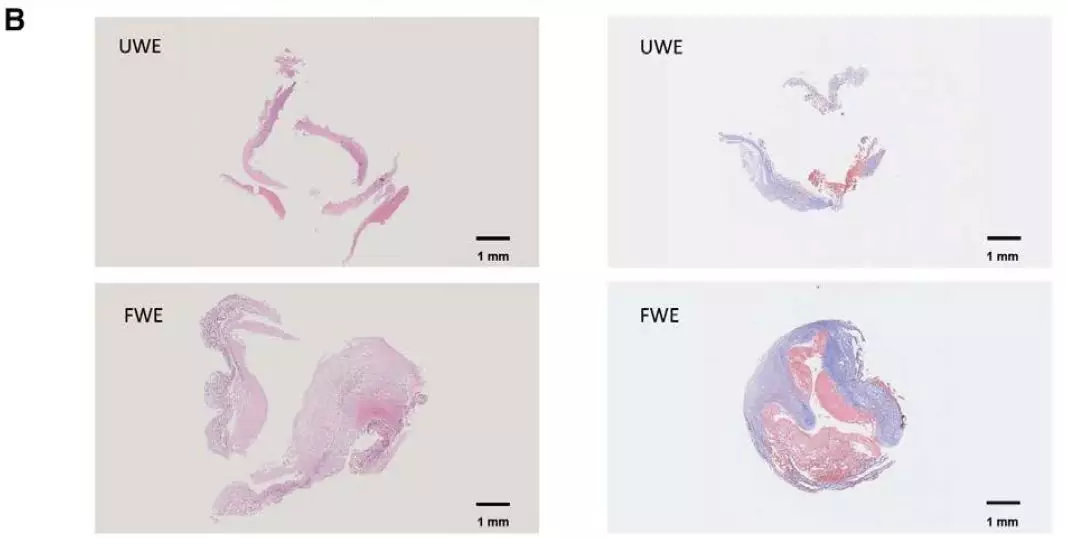

通过瘤壁标本病理检测结果与术前HRVWI强化信号分型对比: CD68和NLRP3在强化的动脉瘤组织中明显上调,瘤壁炎症反应激活(图2-A);与此同时,局部强化(FWE)的动脉瘤组织,比其他强化类型的动脉瘤具有更丰富的粥样斑块(图2-B)。

图2. 动脉瘤组织病理学检测与术前高分辨磁共振分型对照分析。A,动脉瘤壁炎症指标与HRVWI强化信号分型。B,动脉瘤壁粥样硬化程度与HRVWI强化信号分型。